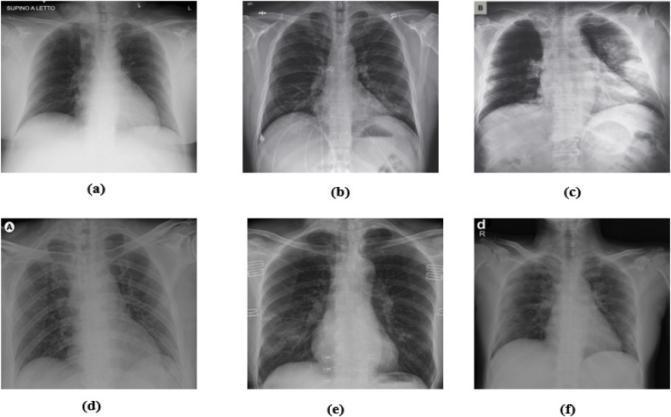

3) The primary chest X ray images have been obtained from the COVID 19 Radiography Database . It contained 1,341 normal, 1,345 viral pneumonia, and 219 COVID 19 patient’s images, which have been taken as primary dataset. However, the distribution of different types of images was not the same. To balance this dataset, we collected 66 images from and added them with COVID 19 images of primary dataset. For other classes (normal and pneumonia), a random under sampling method has been used and

generated balanced instances of each class. Finally, this experimental dataset had been contained 285 normal, viral pneumonia and COVID 19 images respectively. For instance, Figure 5.1.3 illustrates the three types of chest X rayimages, respectively.

We performed experiments to detect and classify COVID 19 using X ray images in two different scenarios. First, we have trained the Dark CovidNet machine learning model to classifyX rayimages into three categories: COVID 1, No Findings, Secondly, the Dark CovidNet model is trained to detect two classes: COVID 19 and No Findings categories. The performance of the proposed model is evaluated using the 5 fold cross validation procedure for both the binary and triple classification problem. Eighty percent of X ray images are used for training and 20% for validation. The experiments are repeated five times as shown. All of the split k pieces are wrapped in folds to use in the validation stage. We have trained Dark CovidNet for 100 epochs. The training and validation loss graphs of the multi class classificationand validationaccuracygraphs.

After preprocessing of the dataset, the final dataset consisted of a total of 900 X ray images. For training and testing the proposed CNN, the dataset was partitioned into two subsets. The training dataset contained 400 COVID 19 X ray images and 400 normal X ray images, making a total of 800 X ray images. The testing dataset similarly contained 100 X ray images, in which 50 X ray images were from each class COVID 19 positive and normal. Then, the training subset containing 800 X ray images has been passed to the model with 25% validation size. So, out of 800 X ray images, with each epoch, 600 X ray images train the model, and 200 X ray Images validate the model. As mentioned in the proposed architecture of the CNN model, it consisted of 38 layers in which 6 are convolutional, 6 max pooling layers, 6 dropout layers, 8 activation function layers, 8 batch normalization layers, 1 flattening layer, and 3 fully connected layers. The CNN model thus achieved an extraordinary performance with an accuracy of 100% with the test data subset used from the processed dataset of this study with a precision of 1.0, with the model parameter values. To evaluate the overall performance, in addition to accuracy, other important metrics have been adopted in this study including F1 score, precision, sensitivity, specificity, and ROC AUC. The scores of these parametersare reported inTable Confusion Matrix :

A public database of pneumonia cases with chest X rays, especially, COVID 19 cases. Data were collected from public sources as well as through agreements with hospitals and physicians with the consent of their patients. Data were divided into 2 folders; normal cases and COVID 19 cases. Each folder contains 25 images with 'jpeg' format and variable size ranging from 700*630 up to 3342*4095.